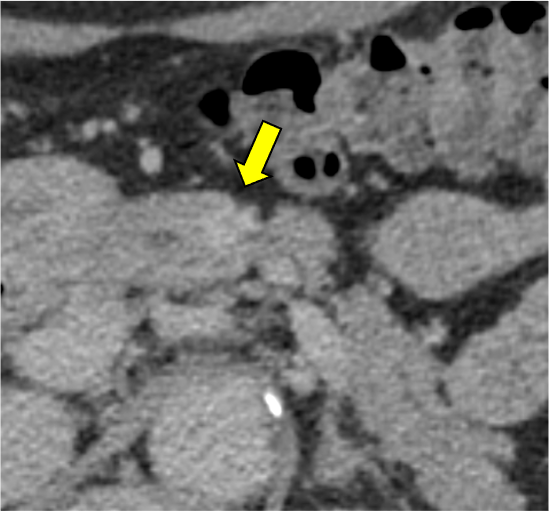

膵ダイナミックCTの膵実質相120kVp画像(図1)で膵体部に限局性萎縮(赤矢印)を認めるが、膵癌を疑わせるような低吸収域は同定できない。遅延相120kVp画像(図2)では萎縮部近傍にごく淡い高吸収域(黄矢印)を認め、線維性間質に富む膵癌の可能性が示唆される。Dual-energy CTの仮想単色低エネルギー画像(図3)およびヨード密度画像(図4)では遅延濃染域が明瞭化しており、膵癌の診断確信度が向上する。膵体尾部切除術が施行され、高分化型浸潤性膵管癌(腫瘍径6mm、pT1a)と最終診断された。術後、補助化学療法が行われ、現在まで無再発で経過している。

CT技術や撮像プロトコル設定について